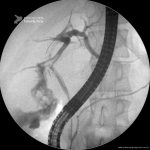

Fístula Biliar

- Imagem da radioscopia mostrando fístula biliar pós-colecistectomia, com identificação de extravazamento de contraste na região do hepatocolédoco médio-proximal.